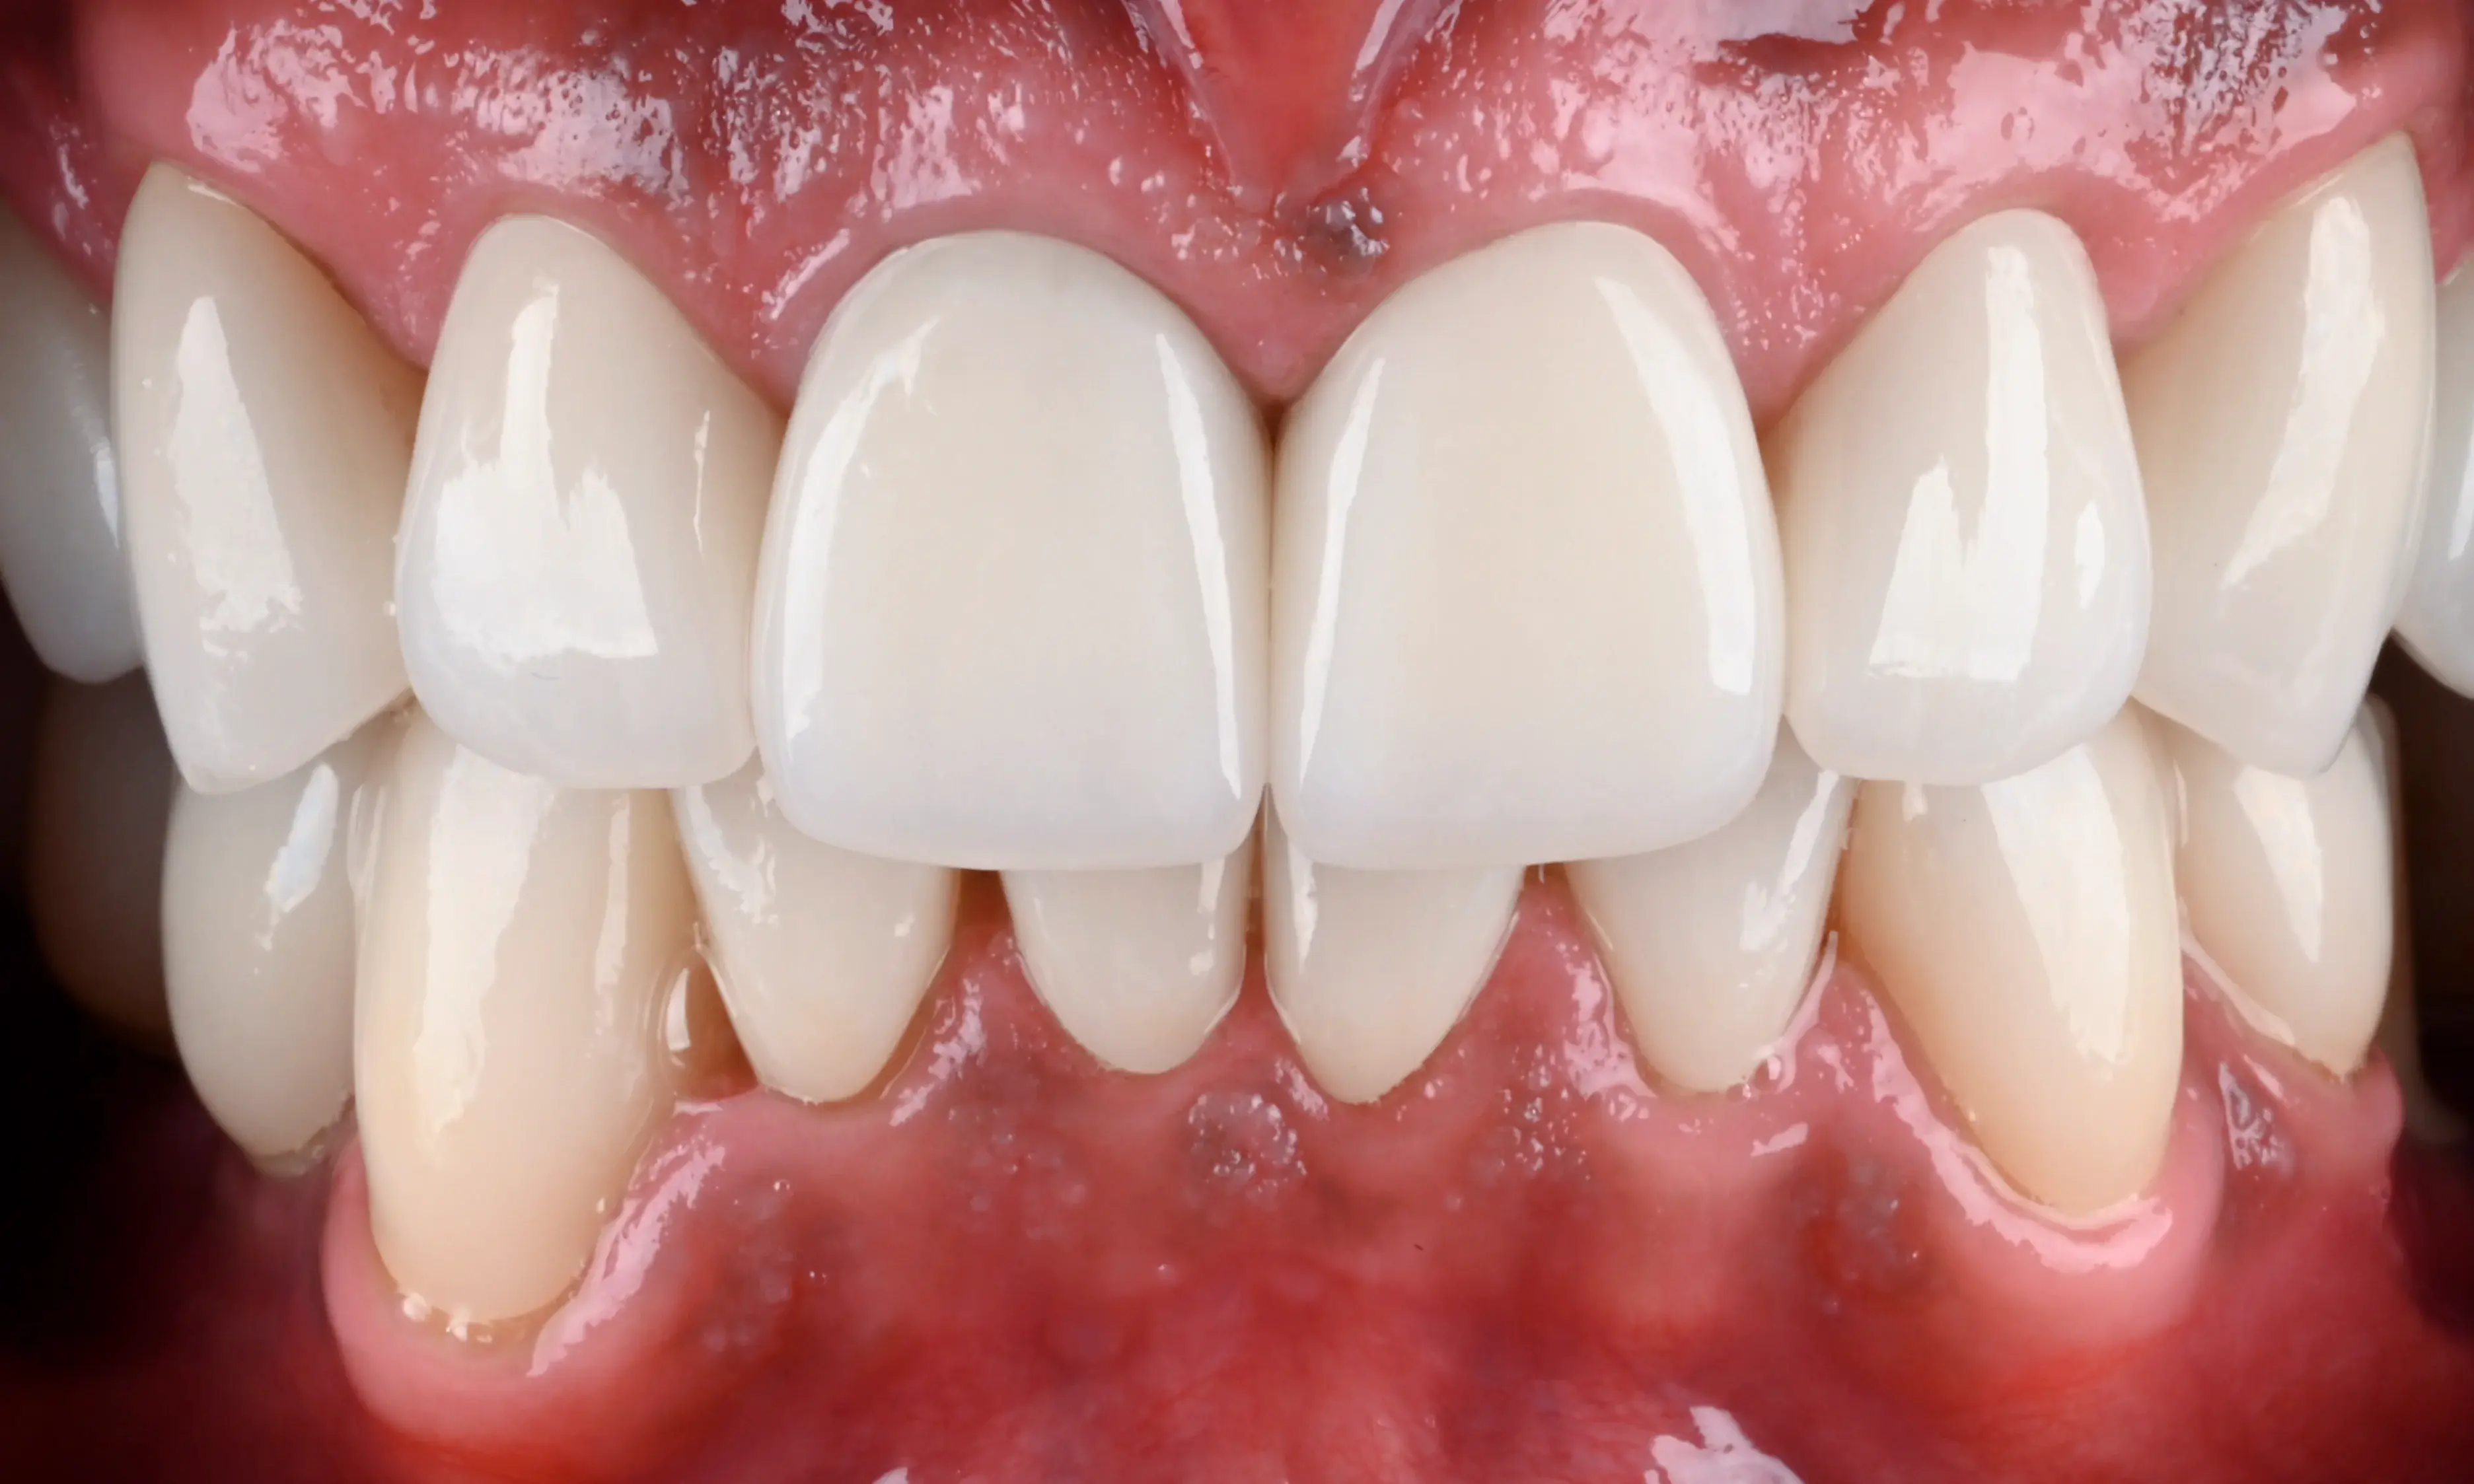

Mit moderner Technologie und optimiertem Workflow: Zahntechnik ohne Kompromisse.

Das Beste aus zwei Welten: Handwerkliche Perfektion beim Schichtkonzept und digitale Höchstleistung durch unser Planungskonzept. Das Ergebnis ist ein hochoptimierter Prozess, der von der ersten Planung bis zur finalen Eingliederung keine Kompromisse zulässt – effektiv und präzise.

Für uns bei dental shapes war dieses Projekt die Gelegenheit, die Grenzen einer modernen Zahntechnik neu zu definieren.